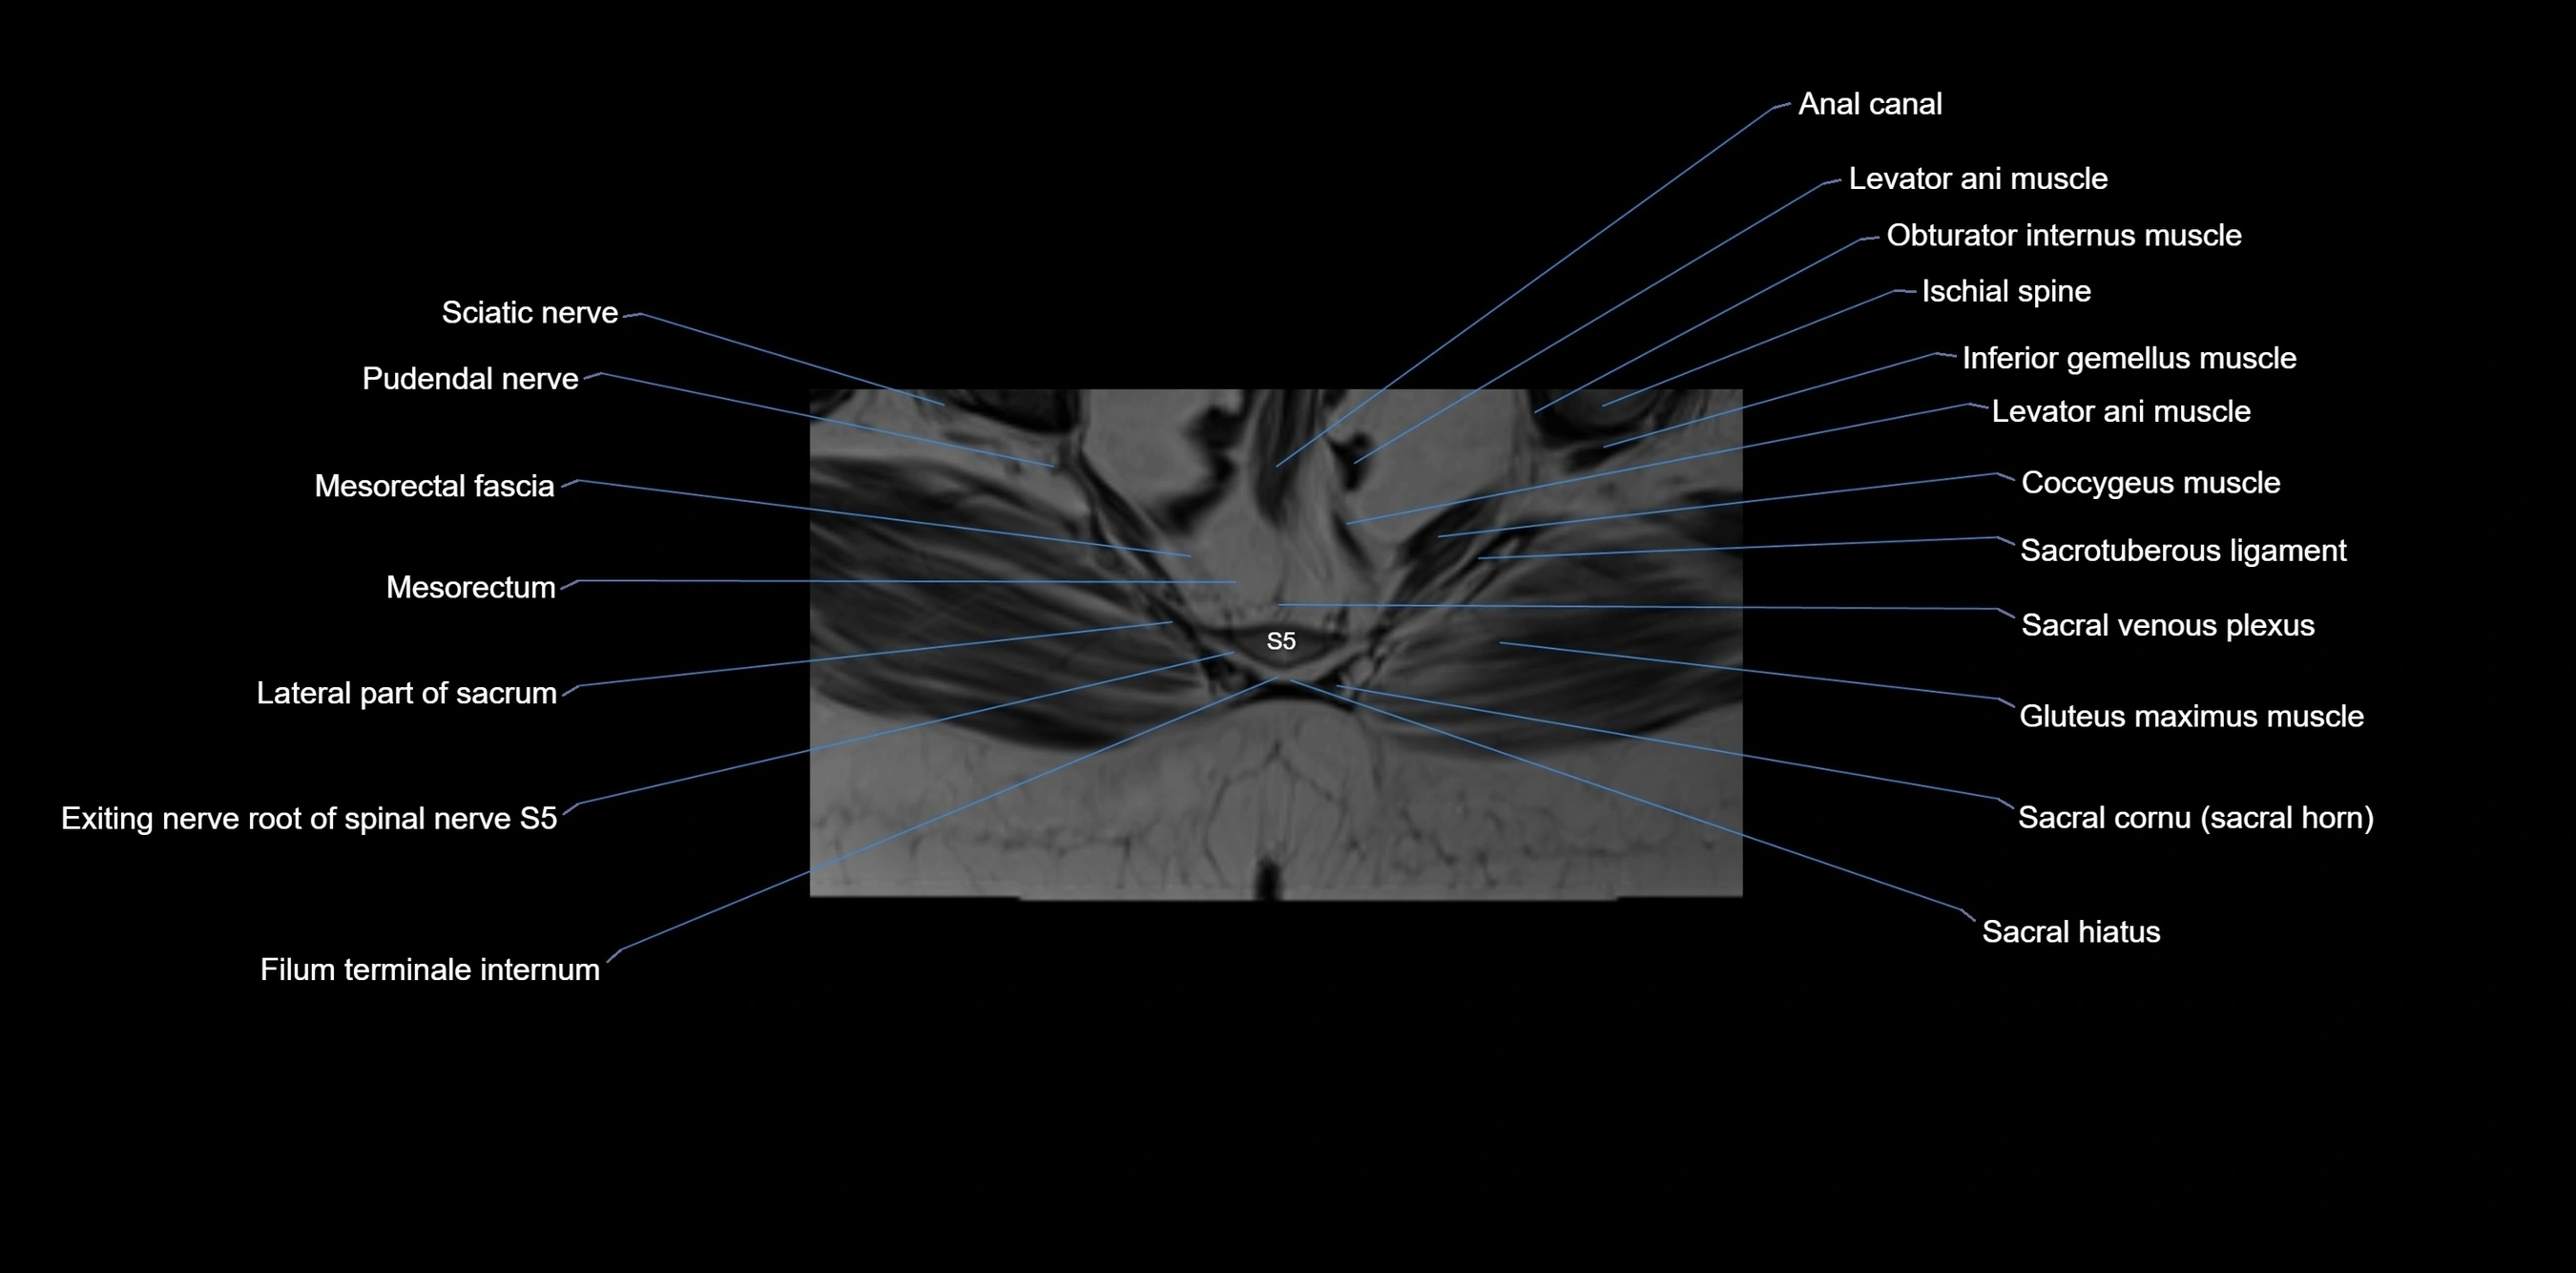

MRI image

image